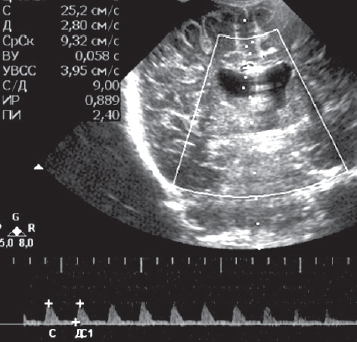

Рис. 4. Краниальная сонография пациента. Дуплекс церебральных сосудов. Результаты измерения скоростных потоков передней мозговой артерии — тенденция к рестриктивному типу / Fig. 4. Cranial ultrasound. Duplex of cerebral vessels. The results of measuring the velocity flows of the anterior cerebral artery-a tendency to a restrictive type

В доплеровском режиме выявлен рестриктивный тип церебрального кровотока (рис. 4).